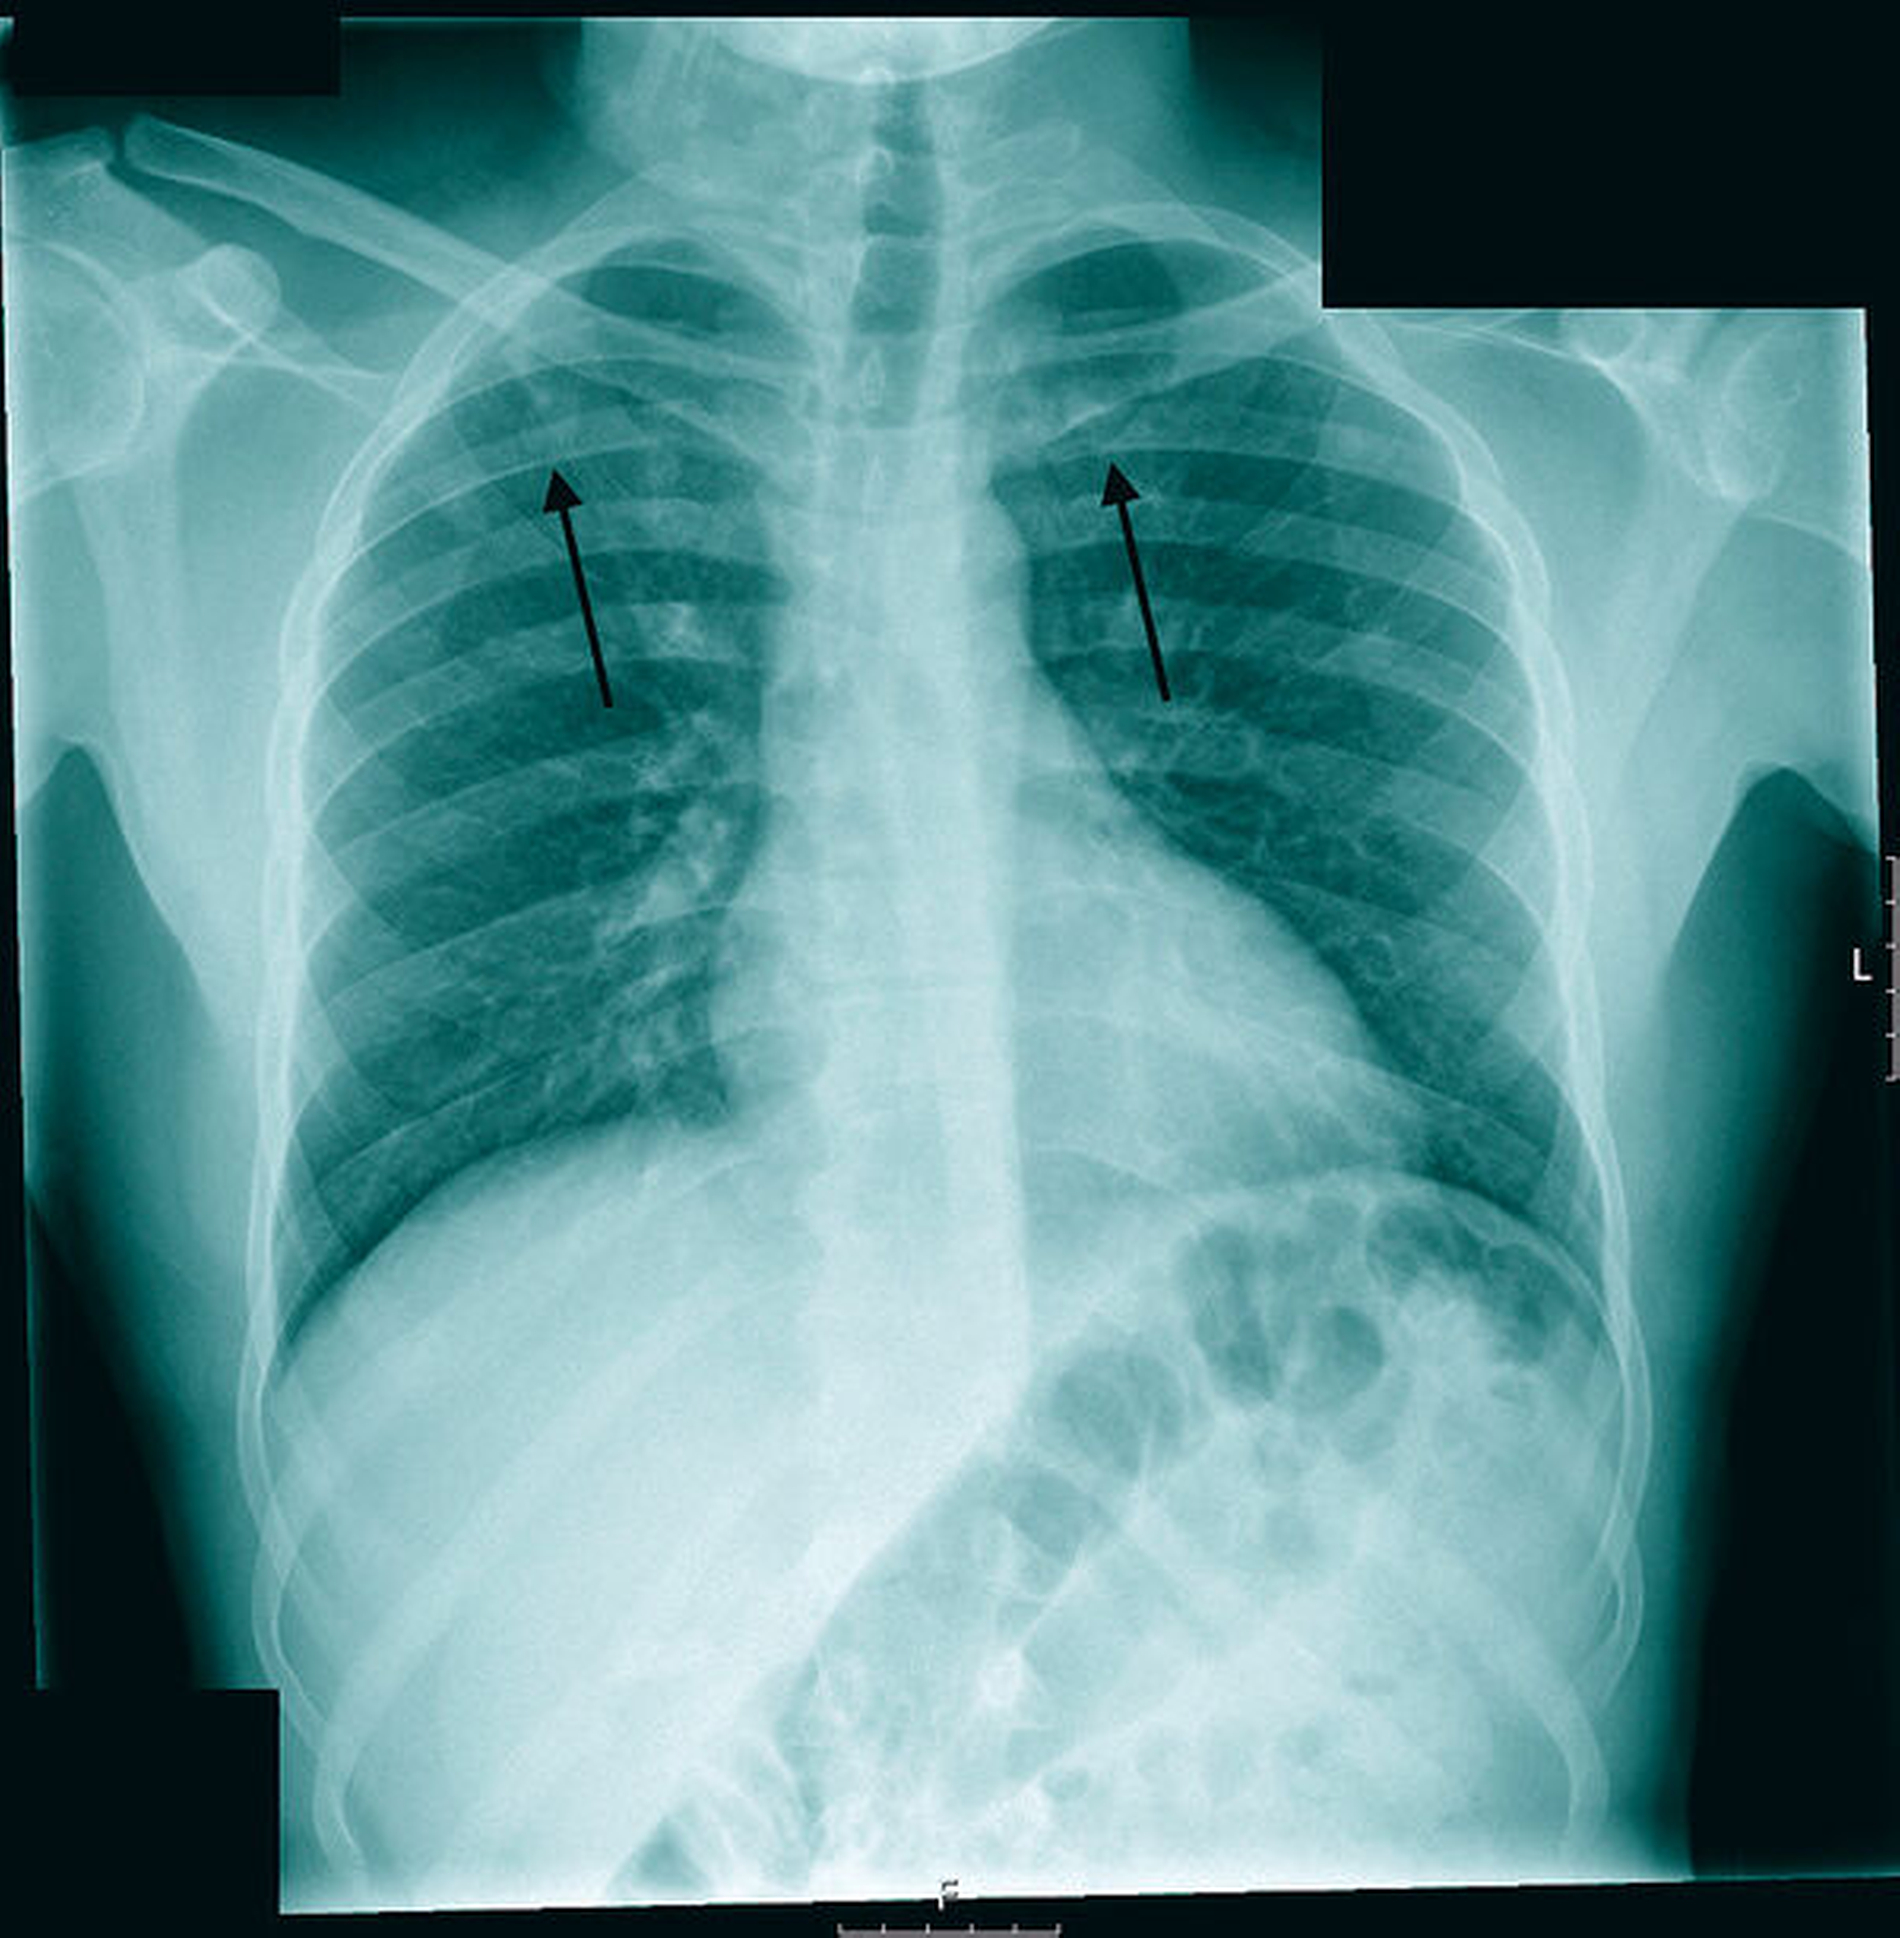

Bei Verdacht auf eine Lungentuberkulose wurden ein Interferon-Gamma-Test (Quantiferon) und eine Röntgenaufnahme des Thorax durchgeführt. In der Röntgenaufnahme zeigten sich korrespondierend zur CT Rundherde und kleinfleckige Infiltrate in den Lungenoberfeldern beidseits mit zentraler Einschmelzung des Herdes im rechten Oberfeld (Abbildung 4). Bei Vorliegen eines positiven Interferon-Gamma-Testergebnisses wurden entsprechend den Empfehlungen zum Ausschluss einer offenen Lungentuberkulose an drei aufeinanderfolgenden Tagen Sputumproben des Patienten entnommen und mikroskopisch mittels Ziehl-Neelsen-Färbung untersucht. Darin zeigte sich vorerst kein Nachweis säurefester Stäbchen, wohingegen in der angefertigten Kultur nach 21 Tagen ein Wachstum von Mycobacterium tuberculosis nachgewiesen werden konnte. Die Serologie des Patienten auf HIV war negativ. Die namentliche Meldung des Patienten und aller Kontaktpersonen erfolgte entsprechend dem Infektionsschutzgesetz an die zuständige Behörde. Es wurde eine sofortige Vierfachtherapie mit den Erstlinienmedikamenten Rifampizin, Pyrizinamid, Insoniazid und Ethambutol eingeleitet und über eine Dauer von zwei Monaten beibehalten. Danach folgte die Kontinuitätsphase über weitere vier Monate mit Isoniazid und Rifampizin.